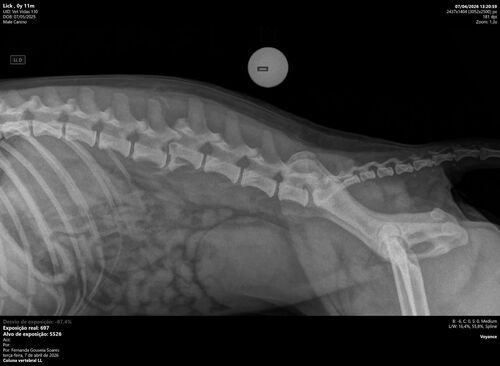

Ontem, nosso cachorro Lucky sofreu um atropelamento e precisou ser levado com urgência ao veterinário. Foi um momento muito difícil e inesperado, e agora ele está em tratamento, lutando para se recuperar 🏥💔

Os custos com atendimento, exames e cuidados já chegaram ao valor de R$ 6.150,00 , e infelizmente não consiguimos arcar com tudo sozinhos neste momento.